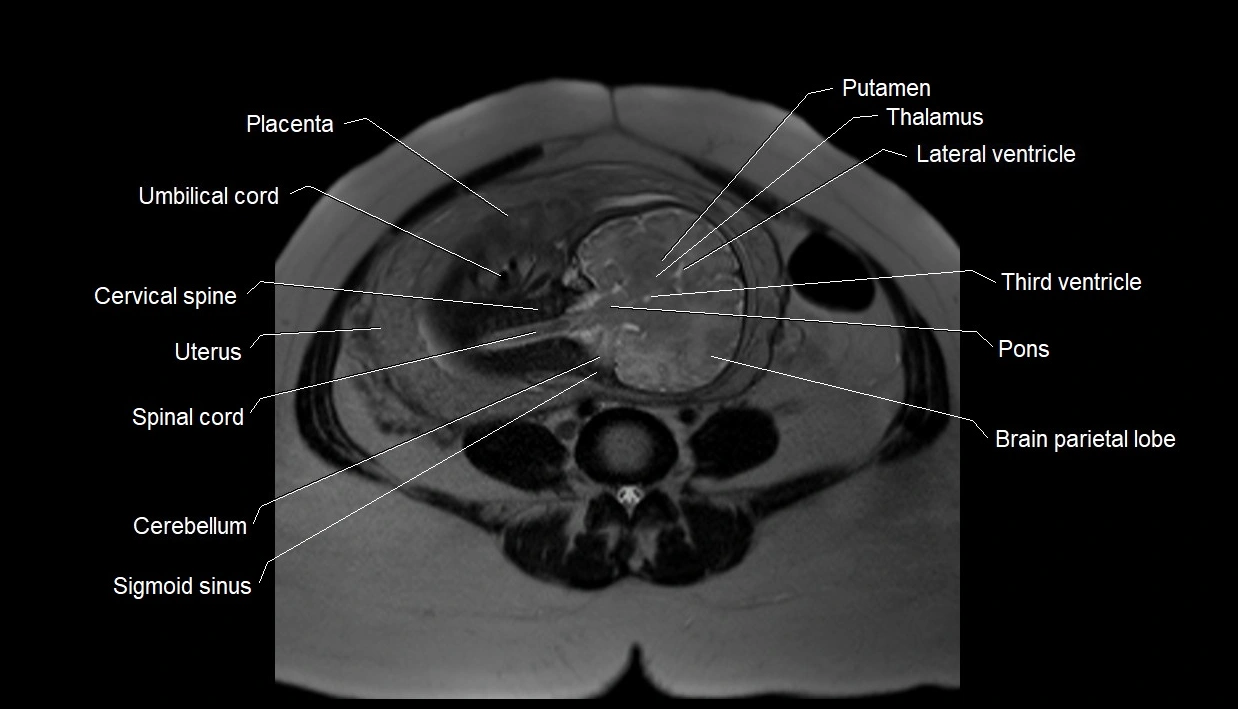

MRI Appearance

T2 HASTE (T2 GRE):

• Amniotic fluid shows very bright hyperintense signal

• Provides natural contrast against fetus and placenta

• Small particles (vernix) may appear as scattered hypointense foci within bright fluid

MRI image

image